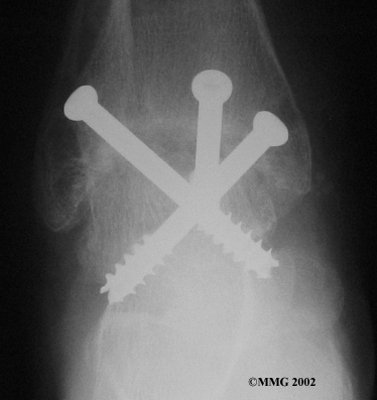

It is important when the surfaces are removed that the angles of the cut surfaces are correct. When the tibia is brought against the talus, the foot should be at a right angle to the lower leg. Once the cuts are made the bones must be held in place while they fuse. This can be done using large metal screws and metal plates if necessary. The screws are usually under the skin and are not removed unless they begin to rub and cause pain.

Inserting the screws

After ankle fusion, the physical therapists at FYZICAL Wilmington can help you learn to walk smoothly and without a limp. Although time needed for recovery varies among patients, an ankle brace will typically replace your cast after eight to 12 weeks. Your surgeon will take X-rays frequently to see if the bones are fusing together. You will probably need to use crutches during the time you wear the cast. As the fusion grows stronger, you will begin to put more weight on your foot when walking.